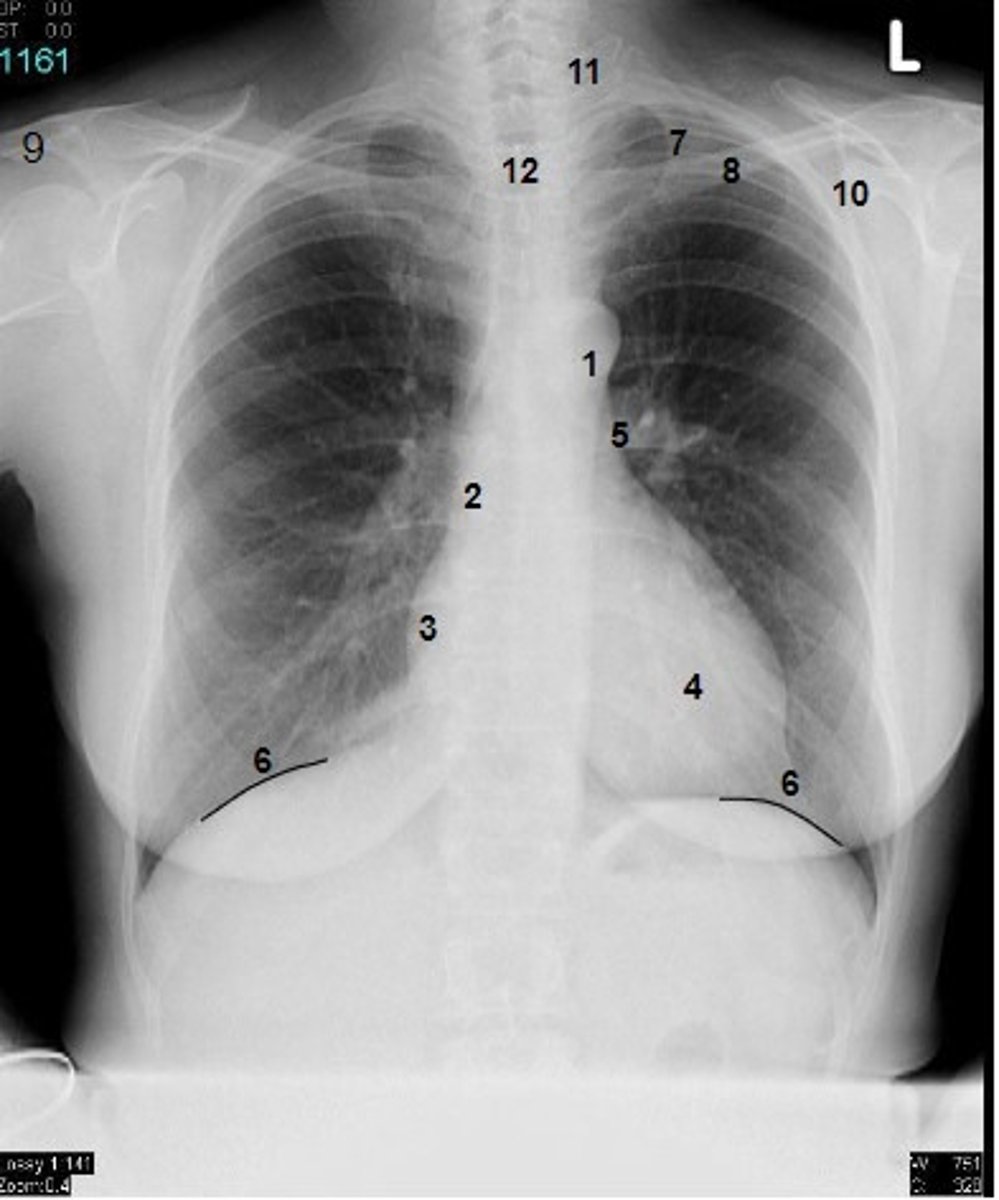

1

at what number is the arch of aorta?

2

at what number is the superior vena cava

3

at what number is the right atrium

4

at what number is the left ventricle

5

at what number is the primary bronchus

6

at what number is the dome of diaphragm

7

at what number is the first rib

8

at what number is the clavicle

9

at what number is the acromion of scapula

10

at what number is the coracoid process of scapula

11

at what number is the transverse process of vertebra

12

at what number is the spinous process of vertebra